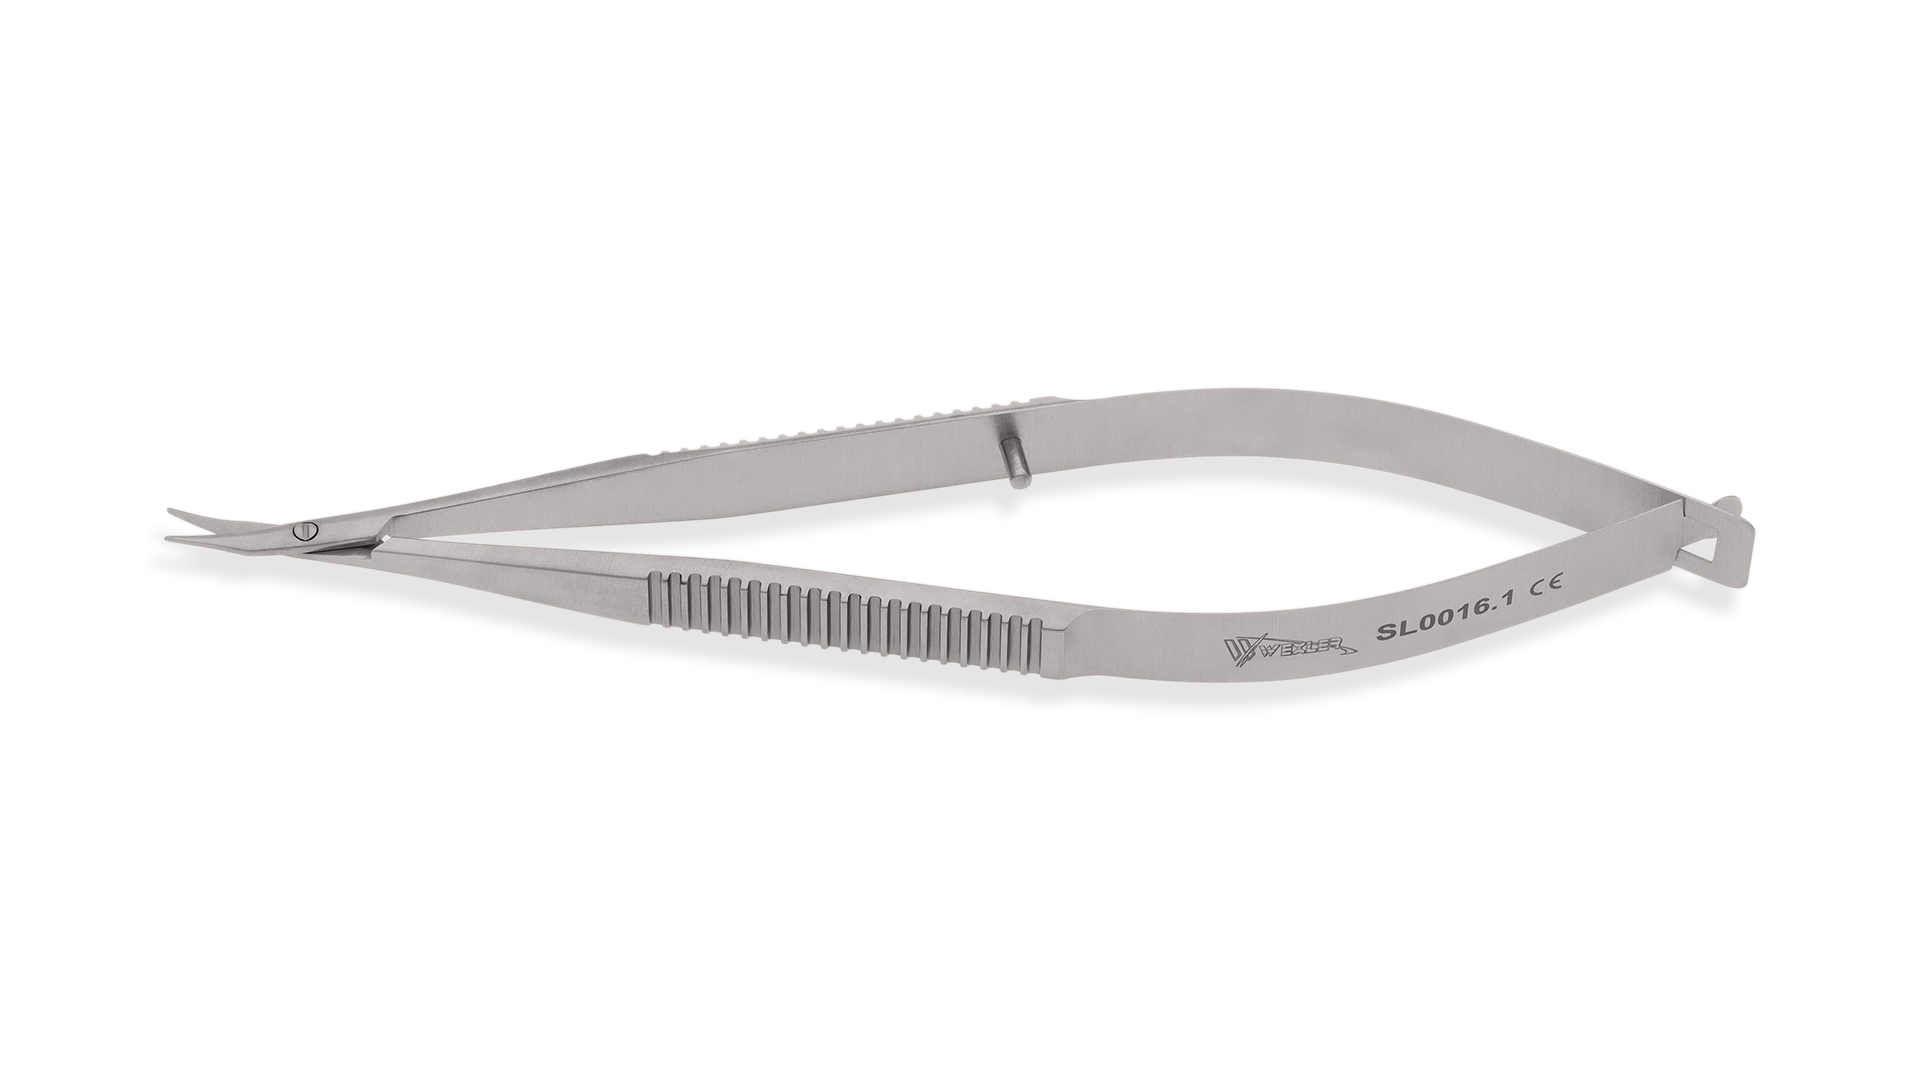

数量限定SALE The Shears Sharp Style – Shear Finishing その他

The Finishing Shear – Style Sharp Shears,

The Finishing Shear – Style Sharp Shears, McPherson-Westcott Conjunctival Scissors | Stainless Steel,

McPherson-Westcott Conjunctival Scissors | Stainless Steel, Amazon.com : SZHLUX 1-Pack Pruning Shears, 6.5'' Gardening,

Amazon.com : SZHLUX 1-Pack Pruning Shears, 6.5'' Gardening, McPherson-Westcott Conjunctival Scissors | Stainless Steel,

McPherson-Westcott Conjunctival Scissors | Stainless Steel, Amazon.com: SINGER ProSeries 9